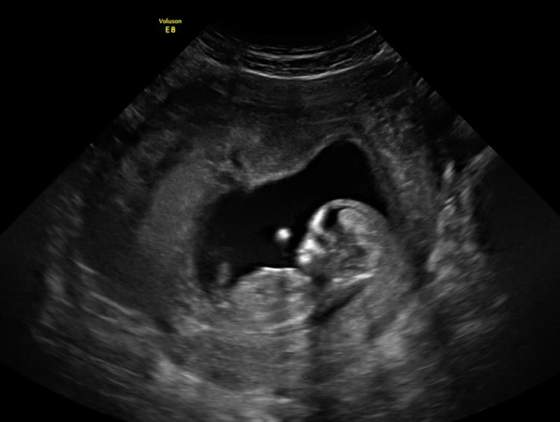

a to moje cudenko z wczoraj :)

12t3d, 63.3mm, puls 159

ale za malo byl ruchliwy (do oznaczenia kilku parametrow nie chcial pozowac), wiec za tydz powtorka :)